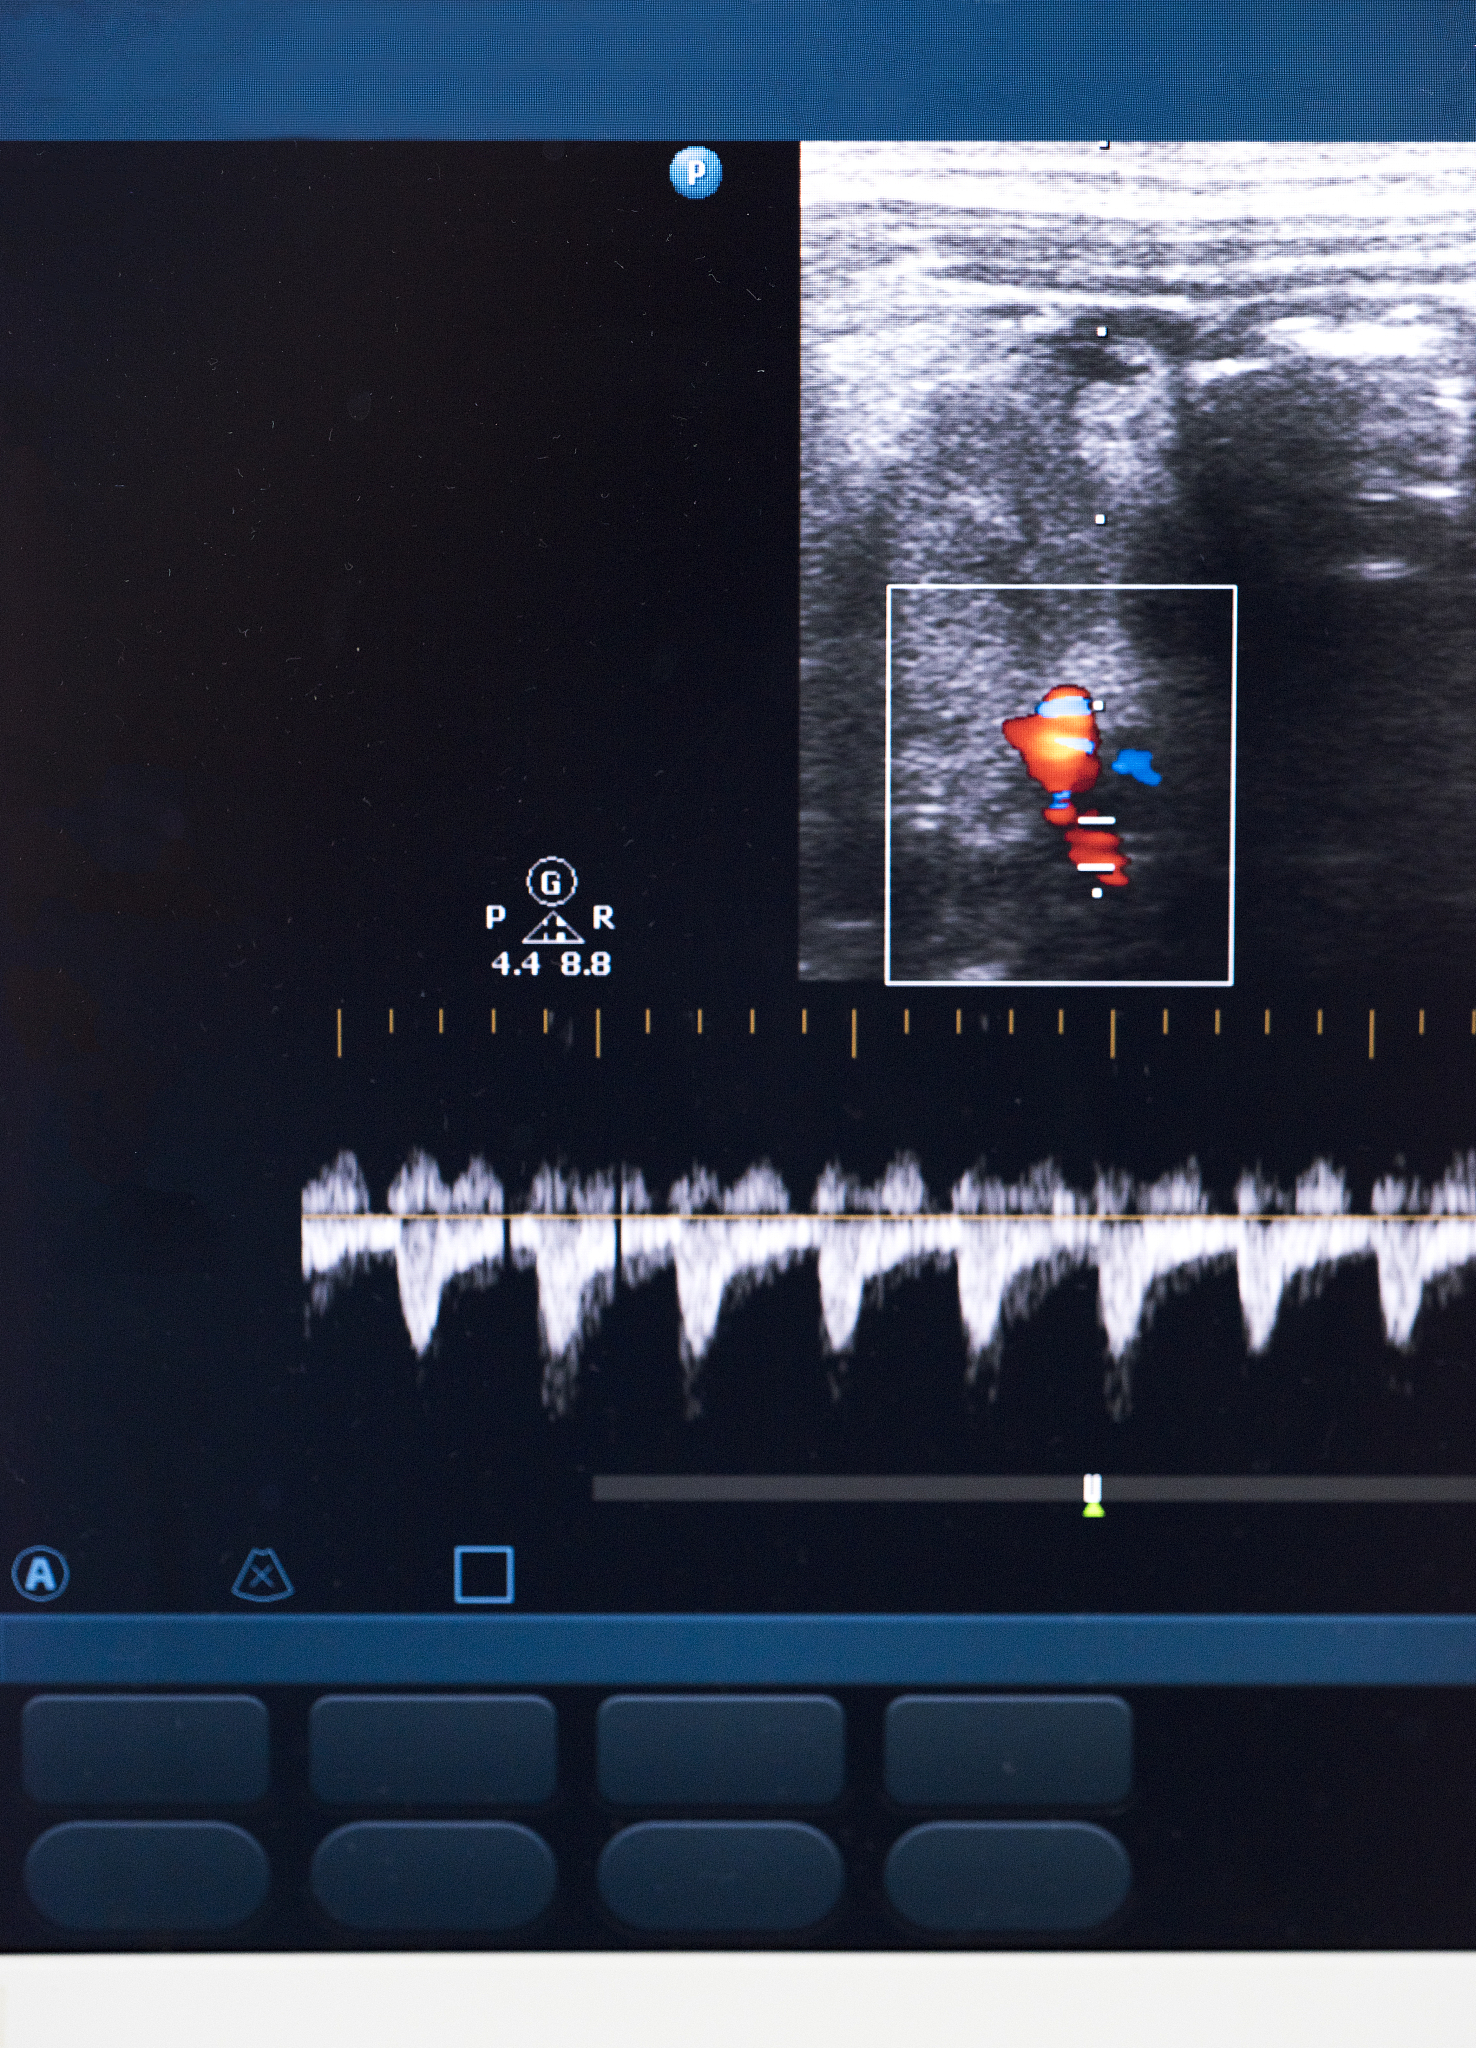

彩色多普勒超声在布加综合征患者TIPS术后随访中可以用于评估TIPS通畅情况和血流动力学状态,具有非侵入性、易操作、无辐射、无副作用等优点。与CTV相比,彩色多普勒超声的灵敏度和特异度可以根据以下公式计算:

灵敏度和特异度是评价一种检测方法的重要指标,灵敏度越高表示该检测方法能够有效地检测出真实存在的病变,特异度越高则表示该检测方法能够较好地排除不存在的病变。在TIPS术后随访中,彩色多普勒超声的灵敏度和特异度的高低可以反映其检测TIPS通畅情况和血流动力学状态的准确性和可靠性,对于指导患者后续的治疗和管理具有重要的临床意义。